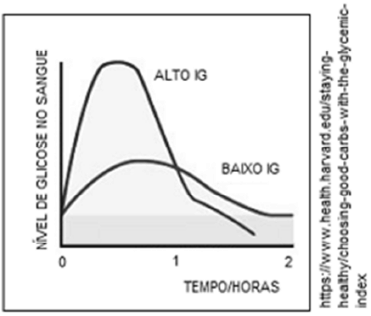

O gráfico a seguir mostra, de forma genérica, os níveis de glicose no sangue, após a ingestão de alimentos com alto ou baixo índices glicêmicos (IG). O tempo zero indica o momento da ingestão.

Com relação ao gráfico e ao controle endócrino da glicemia, analise as afirmativas a seguir e assinale (V) para a verdadeira e (F) para a falsa.

( ) O gráfico mostra que a taxa de glicose no sangue diminui cerca de uma hora após a ingestão dos alimentos. Essa redução é consequência da ação da insulina e do glucagon, hormônios esteroides produzidos pelas ilhotas de Langerhans no pâncreas.

( ) O diabetes refere-se a um transtorno metabólico caracterizado por hiperglicemia e distúrbios no metabolismo de carboidratos. Existem dois tipos principais de diabetes: tipo I e tipo II.

( ) Um alimento de alto IG faz o organismo liberar grandes quantidades de insulina para tentar manter normais os níveis de glicose no sangue. Um alimento de baixo IG faz o organismo produzir glucagon, para estimular o fígado a liberar glicose no sangue.

As afirmativas são, na ordem apresentada, respectivamente,